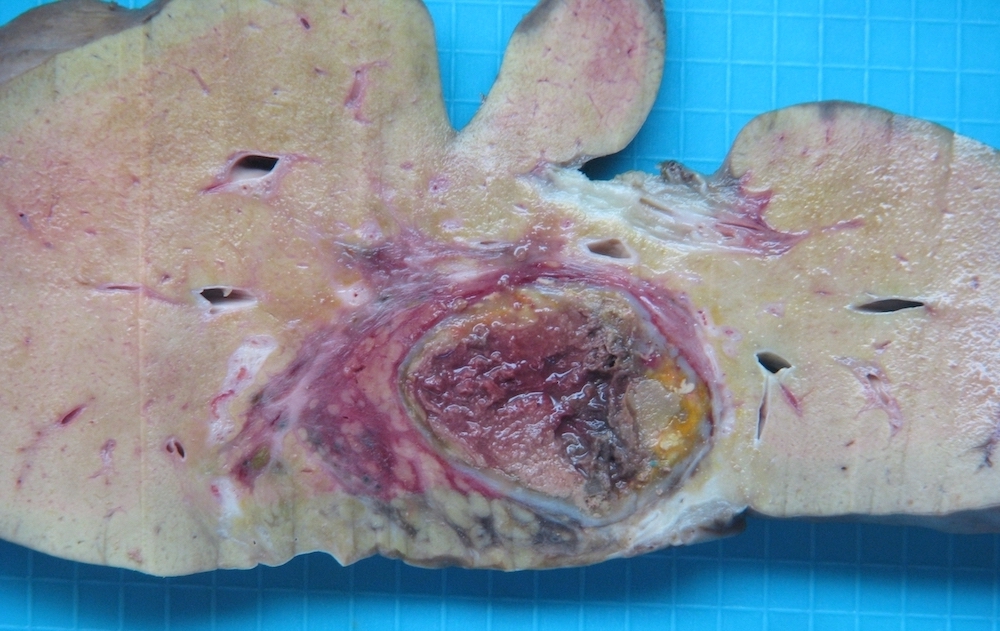

Gross description

- Single or multinodular tumor

- Well defined boundaries

- Tumors usually exhibit a tan-brown cut surface, especially in the fetal subtype (Medicine (Baltimore) 2018;97:e9647)

- Small cell undifferentiated subtypes have a variegated appearance

- Necrosis and hemorrhage are present in posttreatment specimens

- If osteoid is present, the texture is firm and gritty

Gross images